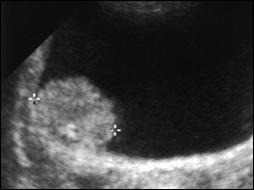

4.2. Ecografia vezicala

Detectarea tumorilor vezicale superficiale, cu grad jos de displazie potential curative, prin tehnici non-invazive ramane o problema nerezolvata [103].

Ecografia vezicii urinare poate aduce date generale importante in diagnosticul tumorilor vezicale superficiale. Este o investigatie strict morfologica ce prezinta mai multe avantaje, fiind nedureroasa, non-invaziva, nu determina efecte secundare, nu are nici un fel de contraindicatie si este repetabila la nesfarsit.

Ecografia vezicii urinare se poate executa pe cale abdominala, transrectala sau transuretrala. Tumorile vezicale apar la ecografie ca mase exofitice, ecodense, intracavitare, fixate la perete, care nu-si schimba pozitia odata cu schimbarea pozitiei pacientului, cu perete vezical normal adiacent tumorii.

Figura 34. a,b. Aspecte ecografice de tumora vezicala - transductor abdominal.

Figura 3 a,b) Aspecte ecografice de tumori vezicale. Formatiuni exofitice protruzive intravezicale.

Unele studii acorda ecografiei posibilitatea de a diagnostica o tumora vezicala in proportie de 80% [85]. Cu toate acestea, ea nu poate pune diagnostic de certitudine, ci completeaza celelalte investigatii.